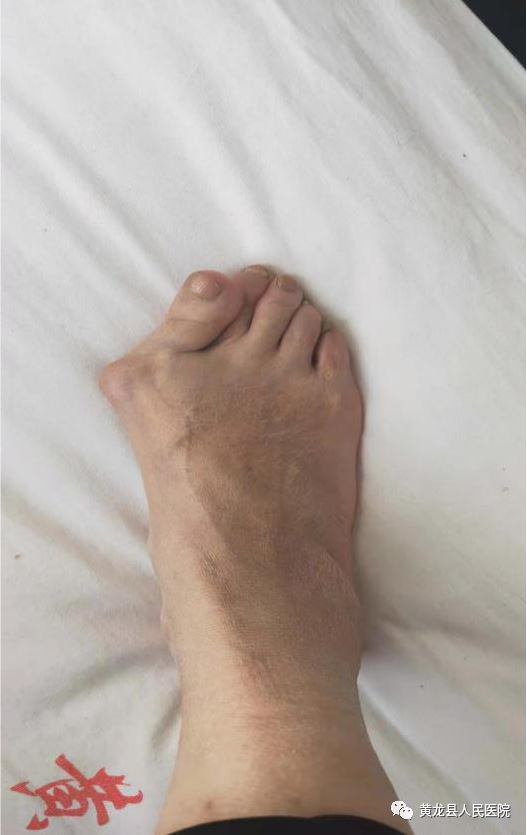

术前外观 术后外观

以上大家看到的影像图片,是一位58岁的女性患者,由于双足踇趾畸形3年余,剧烈疼痛导致穿鞋及活动严重受限。3年前,患者出现双足踇趾向外偏斜,当时畸形不严重,踇趾内侧稍红肿,未予诊治,1年前右足踇趾内侧疼痛明显,活动后疼痛加剧,只有休息后才能稍缓解。患者于1月11日来到黄龙县人民医院外科就诊,经过外科主任方继荣详细询问病史及仔细体格检查后,将患者收治入院治疗。结合患者病情,多方考虑需手术效果最佳,告知患者及家属得到同意。术前,考虑到患者年龄稍微偏大,手术有风险。方继荣带领外科医师对手术风险做了充分评估,对手术方案进行多次讨论,制定了详细周密的手术方案,最终于1月14日上午顺利进行手术。方继荣主刀,在外科医师及手麻科积极配合下,仅用不到1小时,手术顺利完成,达到了术前预期效果,经过手术治疗后,患者脚部成功恢复了美丽的外观,患者及家属对手术效果表示非常满意,向医务人员多次表示感谢。